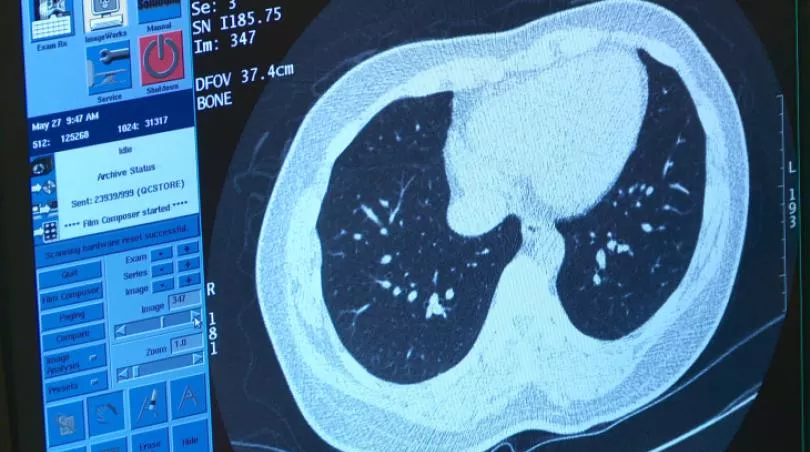

「低劑量電腦斷層(LDCT)」是台灣近年推動的篩檢肺癌方式之一,專家指出,LDCT可提高早期肺癌的檢出率,能有效提高整體肺癌患者的5年存活率;衛福部也表示,透過篩檢可降低重度吸菸者約2成肺癌死亡率。

不過近期LDCT也因存在偽陽性、偽陰性與過度診治等風險而引發討論,衛福部對此強調,臨床上並非一篩檢發現結節就會馬上切除,通常會在尺寸大於0.8公分,且有惡性特徵時才會考慮動刀;目前也已導入AI輔助判讀,以降低不必要醫療風險。

衛福部說明,LDCT是一種輻射暴露較低的電腦斷層掃描,是經醫學證實可作為肺癌篩檢的檢查方式, 且能降低重度吸菸者20%肺癌死亡率。

雖然已被驗證能提高患者存活率,不過衛福部指出,LDCT仍有檢出偽陽/陰性的機率,95%透過LDCT篩檢出來的肺部結節,可能是良性。此外,並非所有肺癌都可以藉由LDCT提早發現,且LDCT也有可能導致過度診治,例如可能診斷出患者惡化緩慢的肺癌,這些人就算不接受篩檢,終其一生都可能不會出現症狀或提早造成死亡。

SMC協助諮詢的專家北醫人工智慧醫療研究中心主任陳震宇指出,健保署正積極發展AI判讀系統,希望讓篩檢更精準。在實務上,AI能快速審視LDCT大量影像,找出可疑肺結節,還可以計算肺結節體積,有助進行追蹤比較;臨床上目前AI的準確度已經能幫助醫師提高效率、減少疏漏。